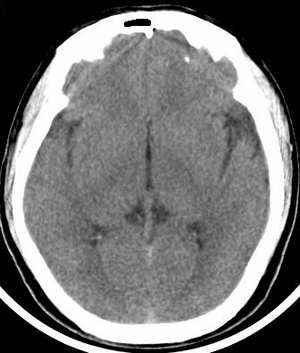

患者 男 45岁,头晕月余,无其它不适。

请大家看看大脑大静脉池里的条状影是什么?脑内静脉?

就是大脑大静脉

应该是大脑大静脉

大脑大静脉